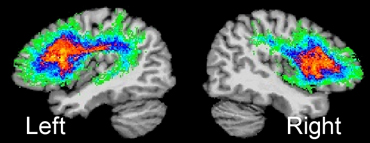

Some neuroimaging data support the idea that people who stutter may have aberrant connections relative to fluent speakers, primarily in the left hemisphere that involves a major white-matter tract (figure 1). In this white-matter pathway, the superior longitudinal fasciculus connects the brain regions involved in speech planning in the inferior frontal region with the auditory regions involved in the sensory feedback of speech sounds, via the motor cortex, which is responsible for speech-motor execution (figure 2). Studies have reported subtle decreases in white-matter integrity in the left superior longitudinal fasciculus in both children and adults who stutter.3-6

Figure 1

Figure courtesy of Soo-Eun Chang

The superior longitudinal fasciculus (SLF) in the left and right hemispheres. SLF is a major white-matter tract that interconnects several brain regions important for speech production. Here, SLF is shown for the left and right hemispheres based on 14 normally fluent individuals.46 The left SLF is greater in fiber tract density compared to the right SLF,47 which underscores its role in supporting speech and language function.